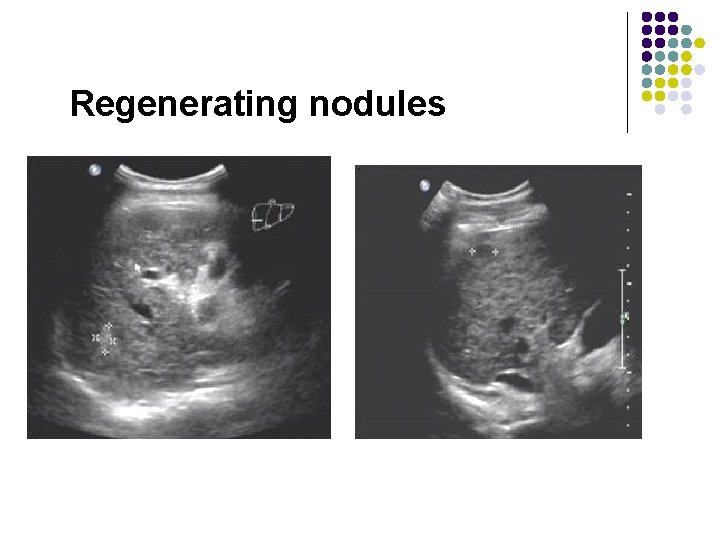

Regenerating nodules

Regenerating nodules